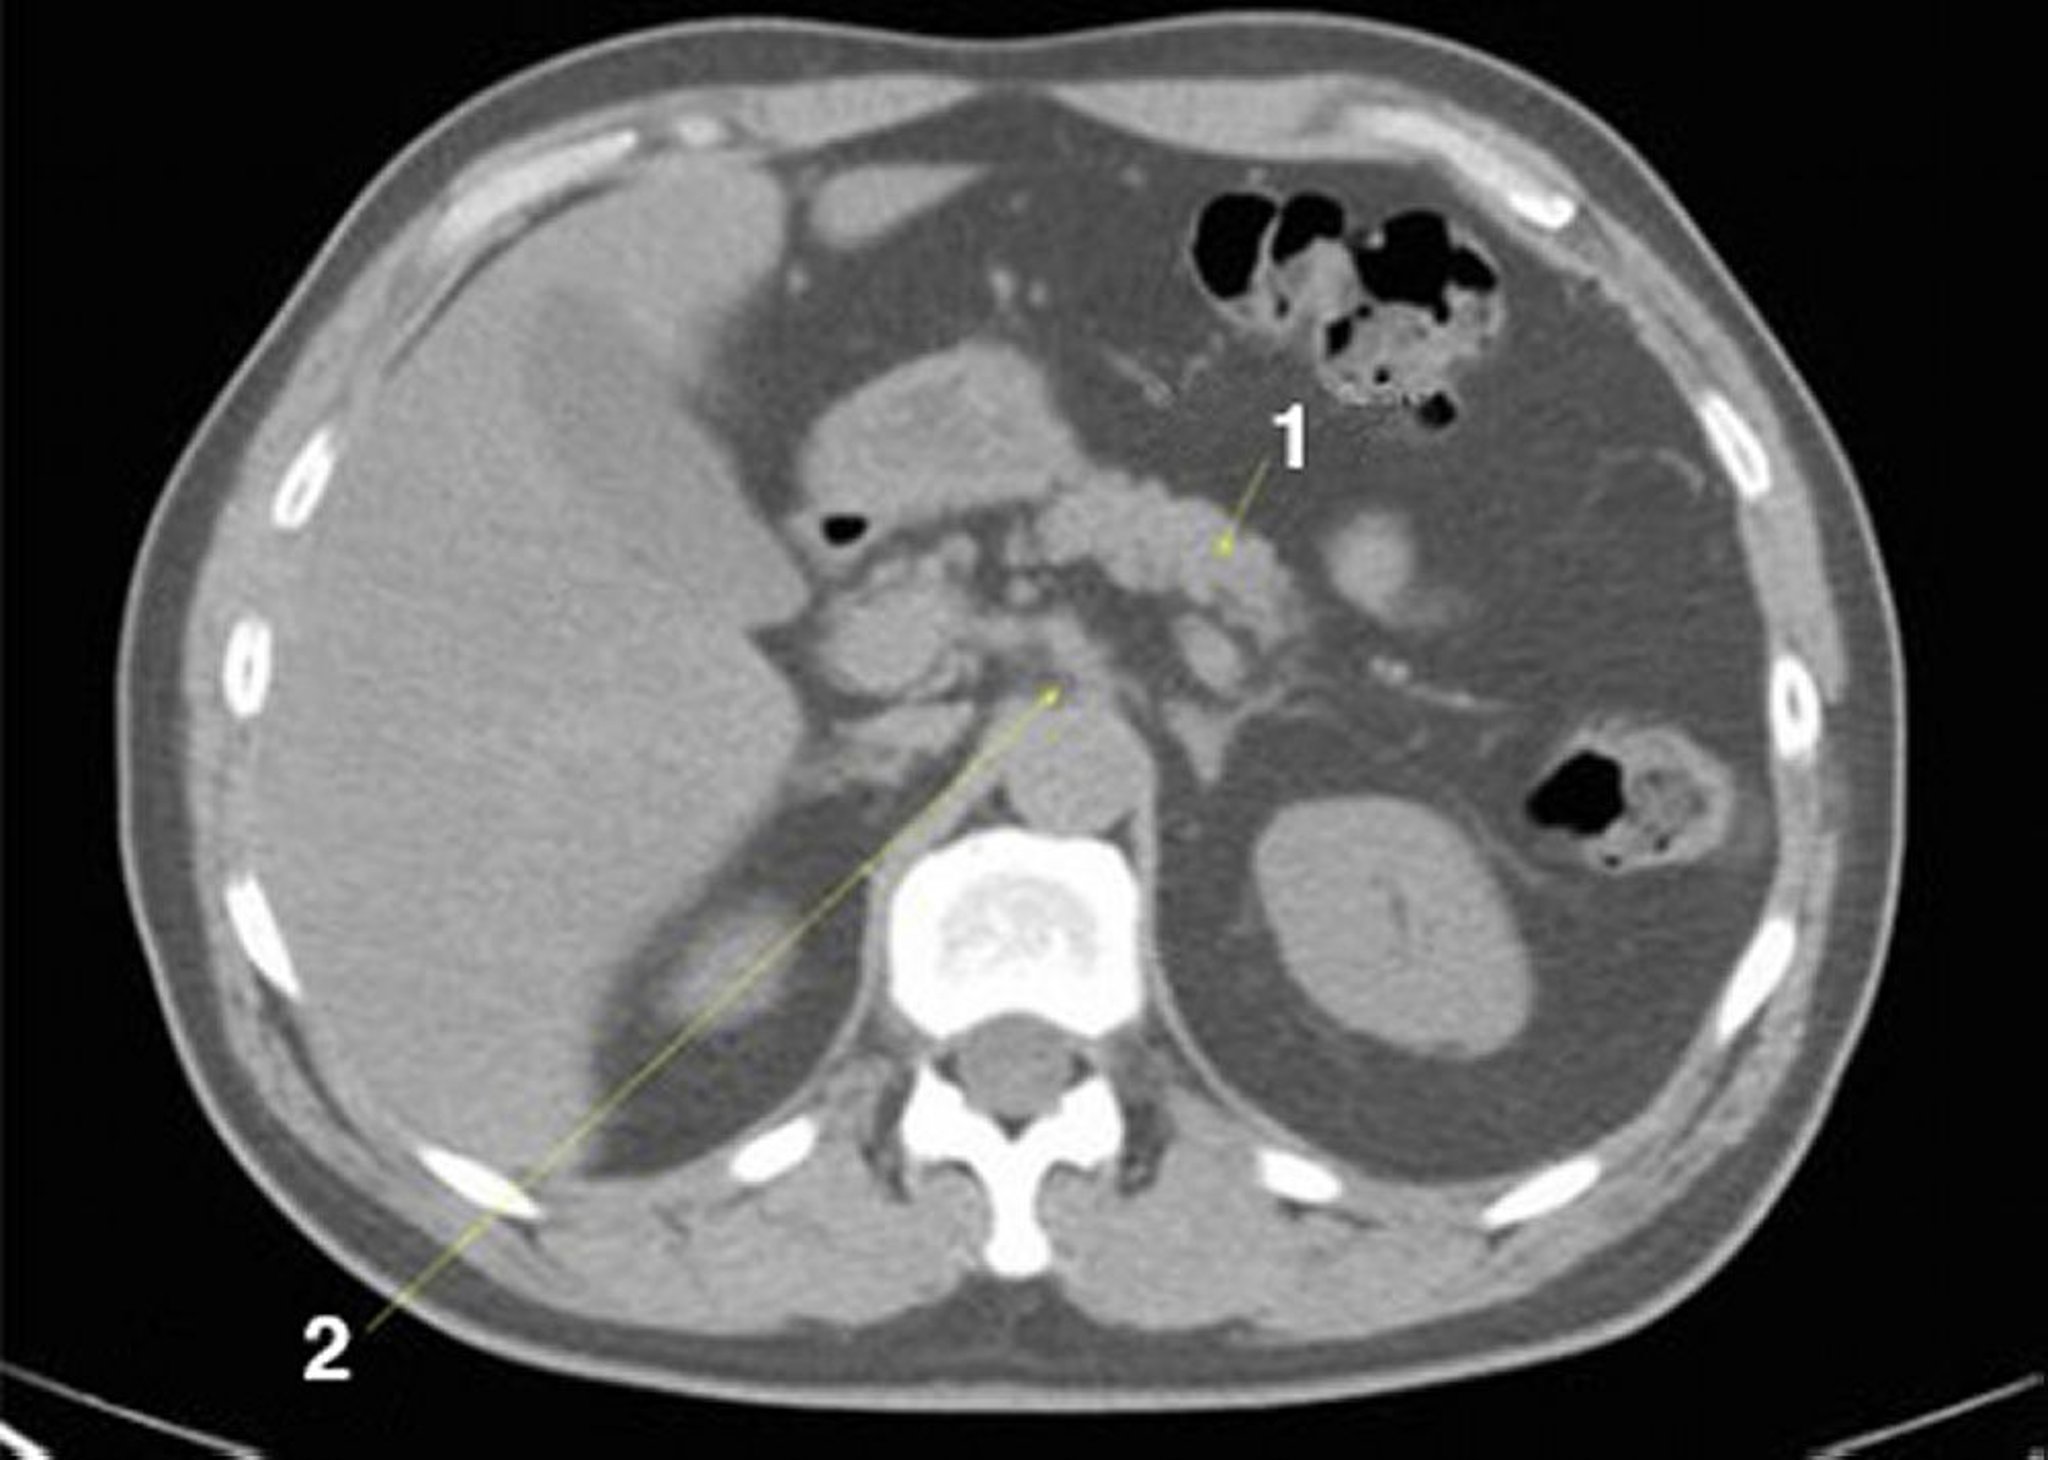

КТ брюшной полости и таза без контраста, демонстрирующая нормальную анатомию (слайд 9)

1 = поджелудочная железа; 2 = чревный артериальный ствол.